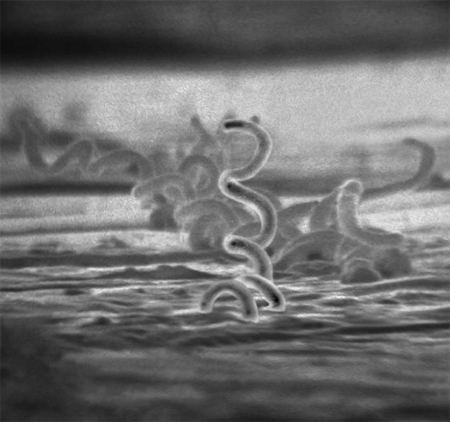

O sexo orogenital é uma importante via de transmissão e, portanto, ela pode ocorrer apesar do uso de preservativo.[1][18] O risco de adquirir sífilis após a relação sexual com alguém com sífilis primária ou secundária está entre 30% e 60%.[19] Outros modos de transmissão são as transfusões sanguíneas e a transmissão transplacentária da mãe para o feto.[Figure caption and citation for the preceding image starts]: Eletromicrografia de Treponema pallidum em culturas de células epiteliais do coelho-de-cauda-de-algodãoCentros de Controle e Prevenção de Doenças (CDC), Dr. Cox; usado com permissão [Citation ends].